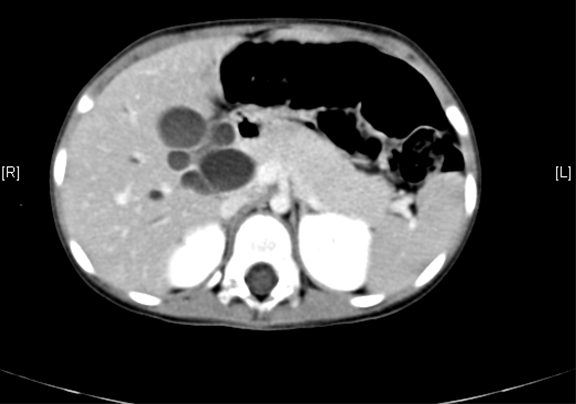

上腹部增强CT:肝内外胆管扩张,考虑先天性胆管扩张症可能性大。

术前CT检查:

平衡期